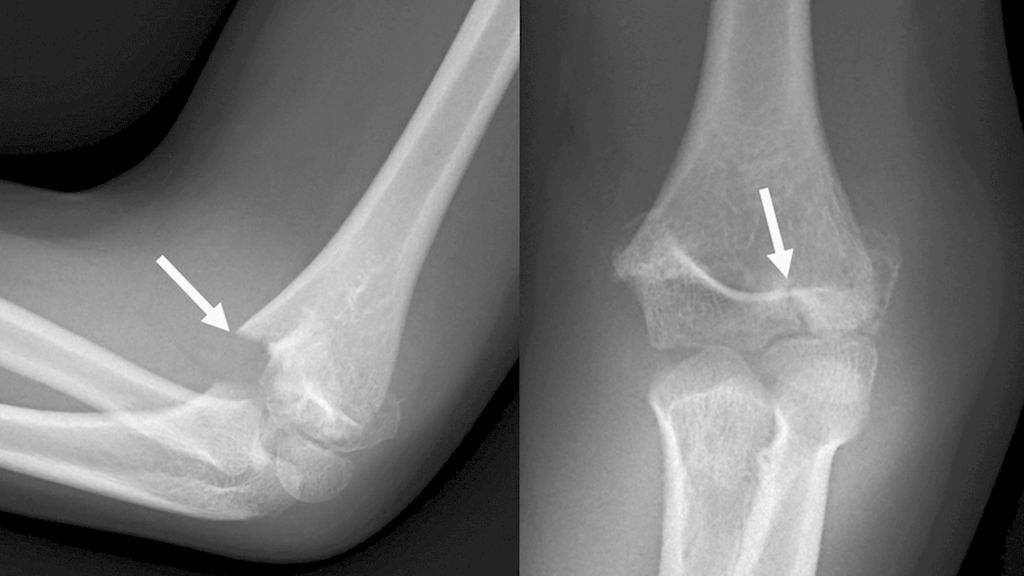

Abb. 3: Zur Unterscheidung von suprakondylären Frakturen ist im seitlichen Röntgen auf den Frakturverlauf zu achten, der bei bikondylären Frakturen die Wachstumsfuge kreuzt und ins Gelenk zieht

Den Standard stellt die konventionelle Röntgenaufnahme des Ellenbogengelenkes in zwei Ebenen dar, wobei bei stark dislozierten Frakturen auf die zweite Ebene verzichtet werden kann, da diese im OP nachgeholt werden kann. Zur Unterscheidung von suprakondylären Frakturen ist im seitlichen Röntgen auf den Frakturverlauf zu achten, welcher bei bikondylären Frakturen die Wachstumsfuge kreuzt und ins Gelenk zieht (Abb. 3). Bei undislozierten Frakturen kann auch eine Sonografie zur Diagnostik durchgeführt werden. Zur Operationsplanung ist beim Adoleszenten bei Mehrfragmentfrakturen ein präoperatives CT oftmals sinnvoll. Eine vaskuläre Verletzung kann mittels Duplexsonografie oder einer Angiografie dargestellt werden.7,8